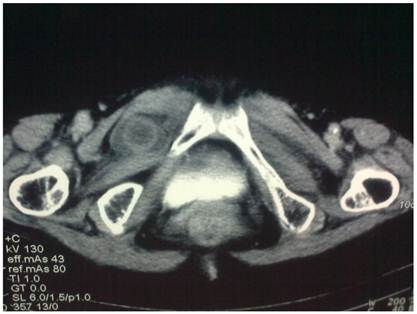

Figure 1

Computed tomography demonstrated a fluid-filled mass located between obturator externus muscles and ipsolateral pectineus.

A 78-year-old woman was sent to our emergency department because of recurrent abdominal pain and constipation for 10 days. The colicky pain was getting worse in recent nearly six days, accompanied with nausea and vomiting. She also complained of intermittent right hip pain with radiation to the medial aspect of the thigh for several months, which worsened with extension, abduction, or internal rotation of right leg. Paracetamol was orally taken irregularly to relieve the pain. She gave birth to 6 kids and denied any history of previous abdominal surgery. The body weight was 38Kg. Physical examination revealed a distended abdomen without tenderness or muscle guarding. Bowel peristalsis was visible, while bowel sounds was absent. No mass was palpated in the bilateral groin. Rectal examination was negative. The adductor reflex of right thigh was absent. The white blood cell count was 13.1×109 /L with 90.6% neutrophils. Serum electrolytes were within normal ranges. The abdominal plain film revealed small intestine obstruction. Enhanced CT scan demonstrated obvious intestinal obstruction with a low density mass in the right obturator canal area (Figure 1). The diagnosis of right obturaor hernia was confirmed and emergency laparotomy was performed. During the operation, a 10cm loop of small intestine was revealed herniated into the right obturator canal (Figure 2). Proximal intestine dilated severely and distal intestine collapsed. The incarcerated intestine was reduced and a perforated lesion was noted. Intestinal segmentectomy and simple suture closure of obturator foramen were performed. The patient was recovered uneventfully and discharged one week after operation. No recurrence was noted within one and a half years of follow-up.